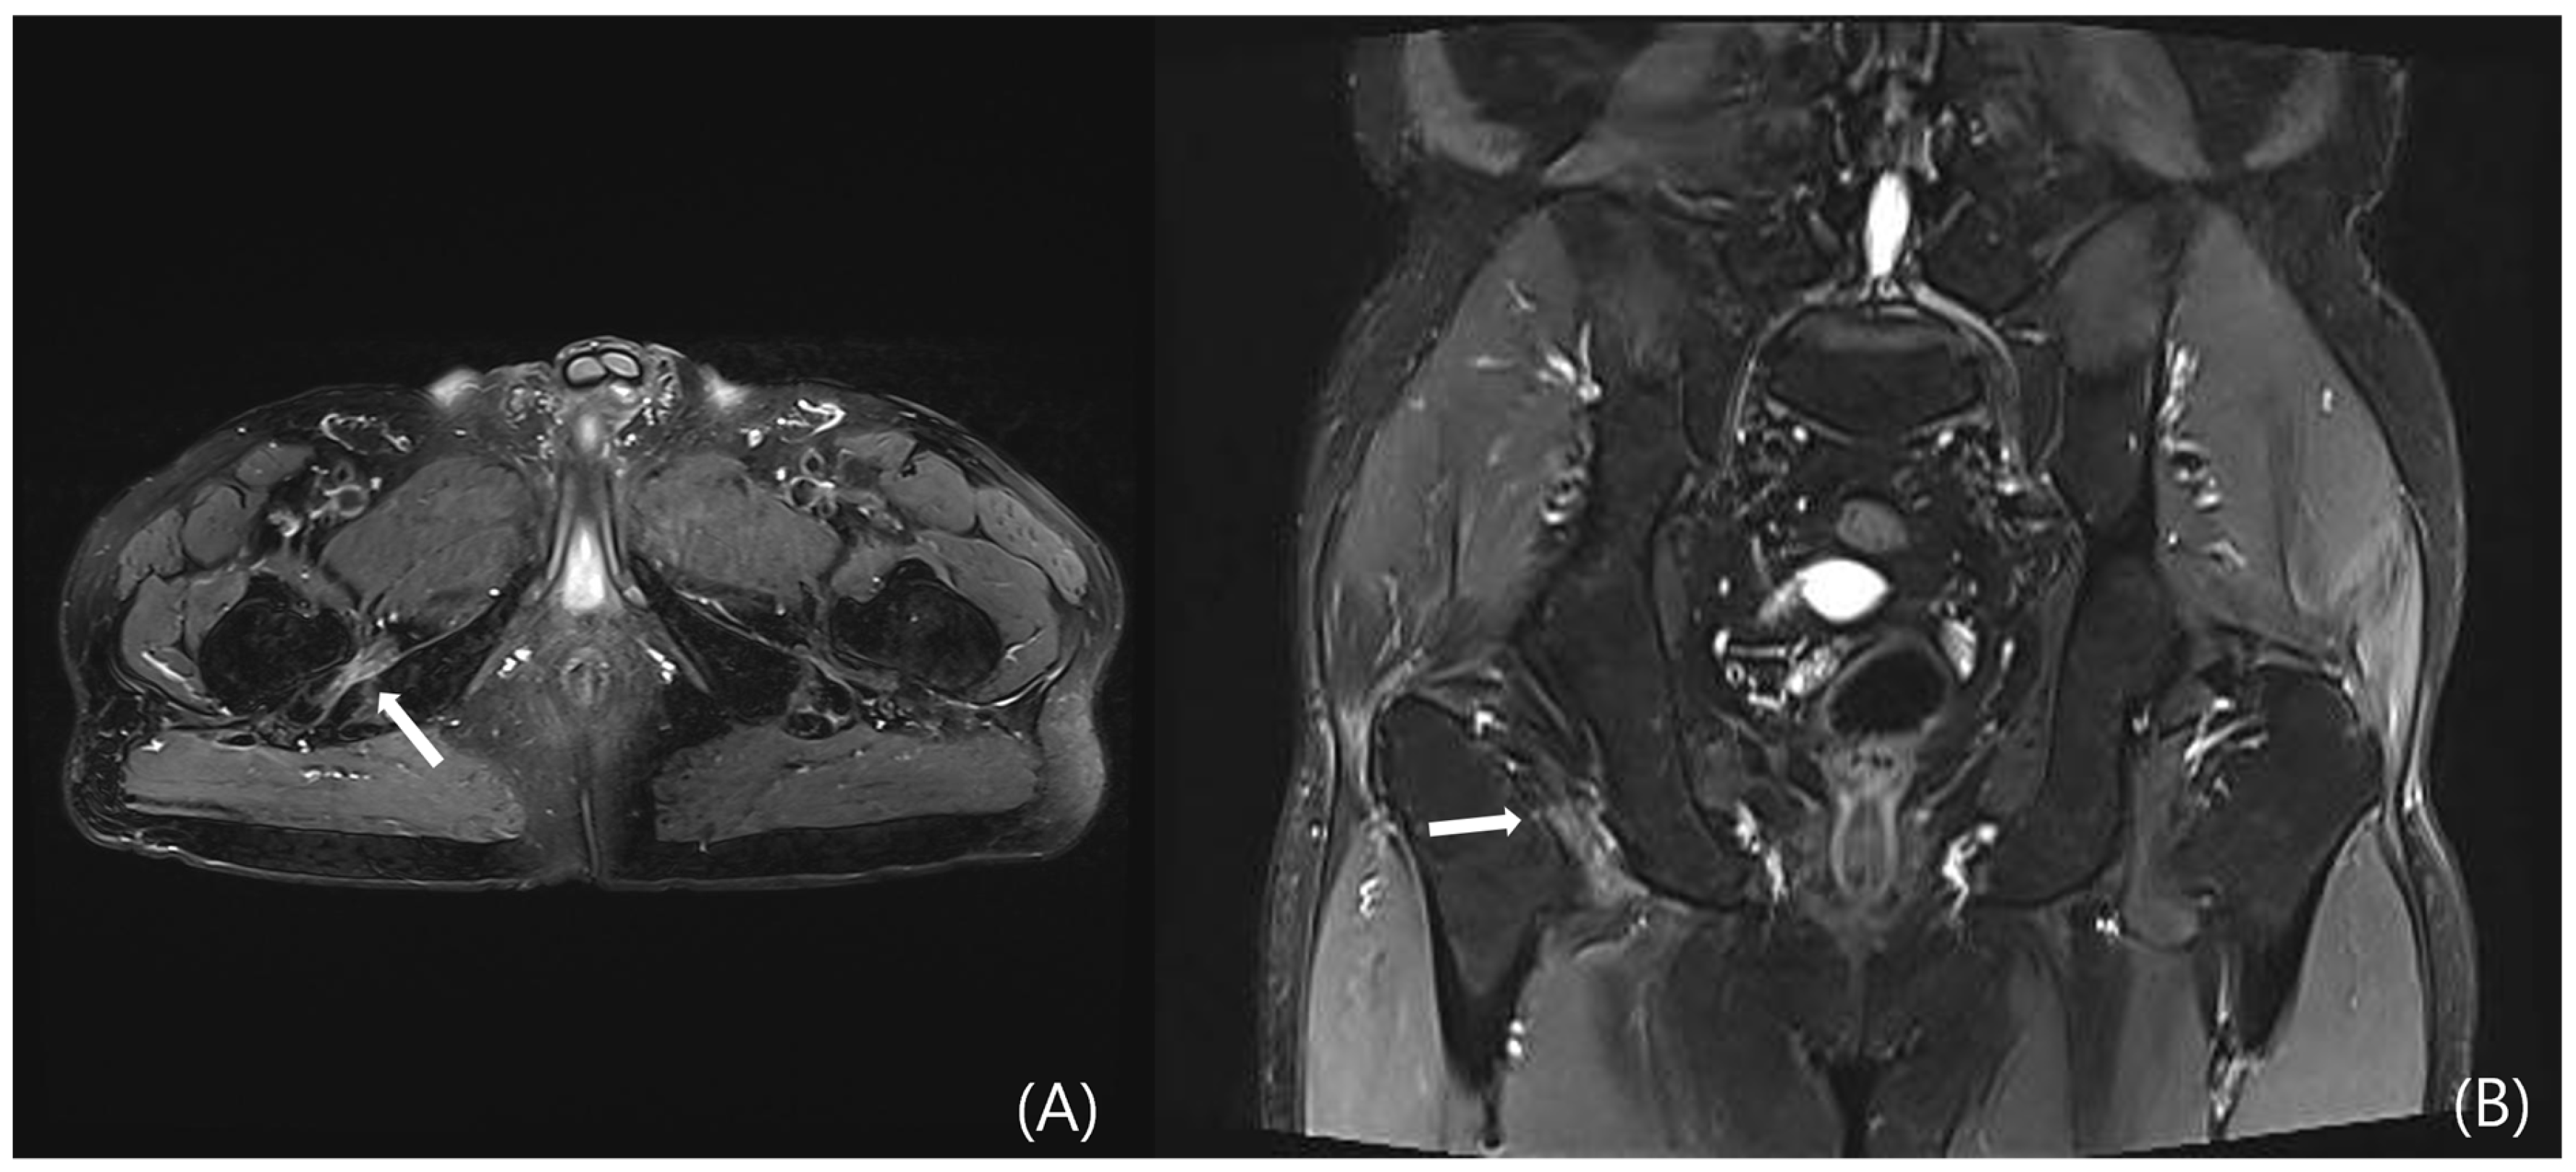

4.3.3. MRI